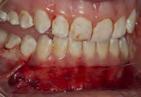

Figura 1. Fotografia inicial, se observa un fenotipo delgado festoneado, estrecha banda de encía queratinizada en zona anteroinferior con sobremordida, apiñamiento y retroinclinación en el maxilar anterior inferior.

En los pacientes con tratamientos de ortodoncia que presentan fenotipos gingivales delgados, pueden estar limitados los movimientos dentales para la corrección de discrepancias esqueletales y malposición dental. Si estas discrepancias y malposiciones dentales, no son bien planeadas por el ortodoncista, puede favorecer a la aparición de recesiones y deformidades mucogingivales.1,2

Paciente femenino de 13 años de edad, acude con sus padres a la clíni ca de periodoncia de la Universidad Popular Autónoma del Estado de Puebla para revisión dental. Al reali zar la exploración clínica, en su aná lisis gingival, la paciente presenta un fenotipo gingival delgado, con estre cha banda de encía queratinizada en el maxilar anteroinferior, edema y eri tema en zona marginal y papilar, acu mulación de biofilm dental en zonas interproximales y marginales, retroin clinación y apiñamiento anteroinfe rior, con una notoria sobremordida y paladar profundo. Posteriormente al realizar periodontograma y aná lisis radiográfico se diagnostica a la paciente con una gingivitis inducida por biofilm dental y según la nueva clasificación del World Workshop del 2017 presenta deformidad mucogin gival alrededor de los dientes por la estrecha banda de encía queratiniza da (Figura 1).